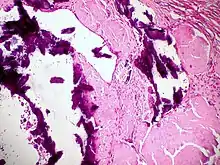

Dystrophic calcification

Dystrophic calcification (DC) is the calcification occurring in degenerated or necrotic tissue, as in hyalinized scars, degenerated foci in leiomyomas, and caseous nodules. This occurs as a reaction to tissue damage,[1] including as a consequence of medical device implantation. Dystrophic calcification can occur even if the amount of calcium in the blood is not elevated, in contrast to metastatic calcification, which is a consequence of a systemic mineral imbalance, including hypercalcemia and/or hyperphosphatemia, that leads to calcium deposition in healthy tissues.[2] In dystrophic calcification, basophilic calcium salt deposits aggregate, first in the mitochondria, then progressively throughout the cell. These calcifications are an indication of previous microscopic cell injury, occurring in areas of cell necrosis when activated phosphatases bind calcium ions to phospholipids in the membrane.